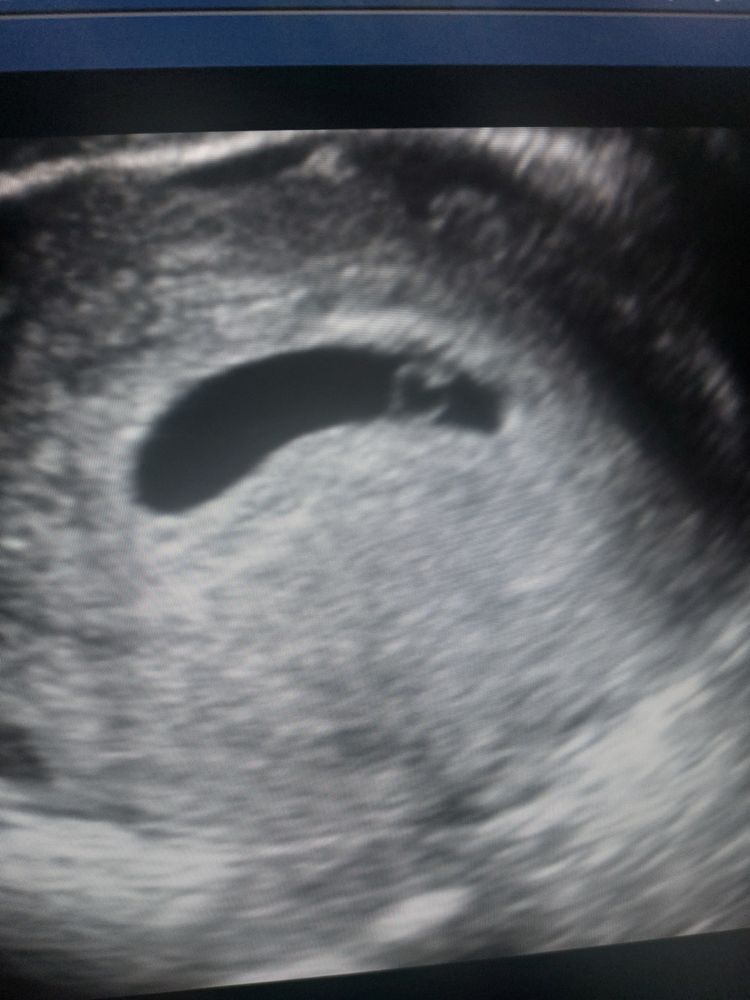

Ровно 4 недели от зачатия или 6 акушерских недель) картина в принципе такая же) колечко с бриллиантом) плодное яйцо 24х8мм, желточный мешочек 3мм, сам эмбриончик 1мм. Сказали, что всё хорошо, только тонус есть. Вот эта белая точка у колечка и есть эмбриончик) так что я думаю, что переживать не стоит и нужно чуть позже переделать узи Изображение